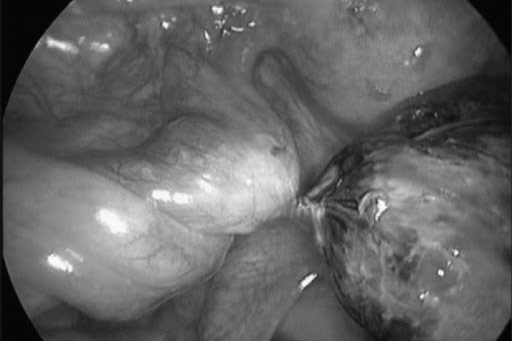

Hình ảnh một u nang buồng trứng bị xoắn nhiều vòng.